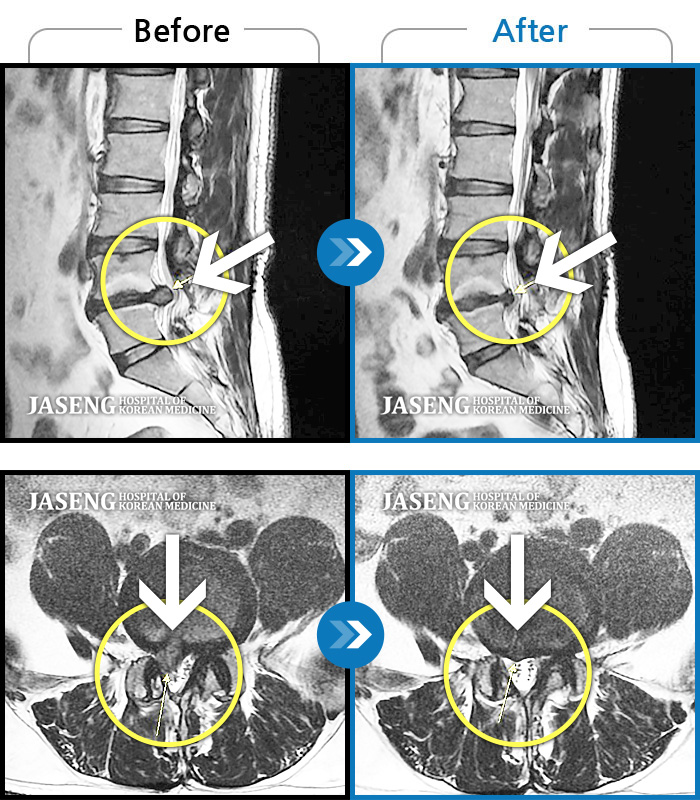

허리디스크

울산 · 정운석 원장

좌측 하지 외측이 저리면서 당김증상 및 감각둔화

촬영시기

2016.12.22 ~ 2022.11.24

2022.12.09